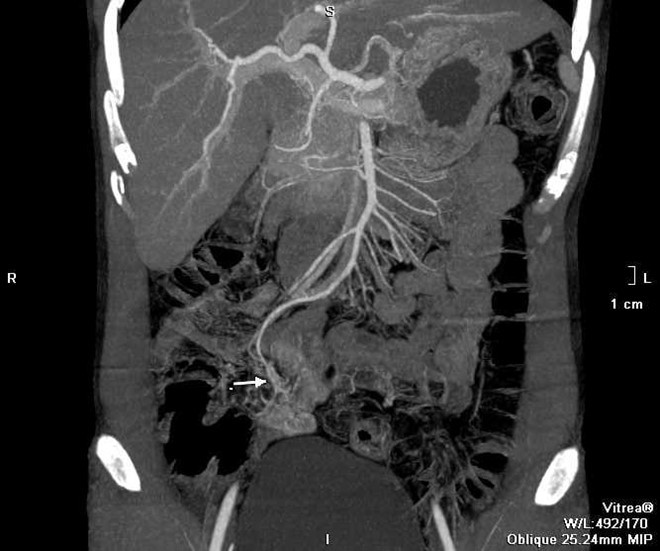

Sau hồi sức tích cực, anh C. được tiến hành chụp CT. Các bác sĩ phát hiện búi dị dạng mạch máu từ một nhánh của động mạch mạc treo tràng trên, nằm ngay trên thành ruột non, đang có dấu hiệu chảy máu. Đây là thủ phạm gây chảy máu kéo dài.

| Hình ảnh CT của bệnh nhân khi vào viện cho thấy mạch máu dị dạng gây chảy máu. Ảnh: BVCC. |